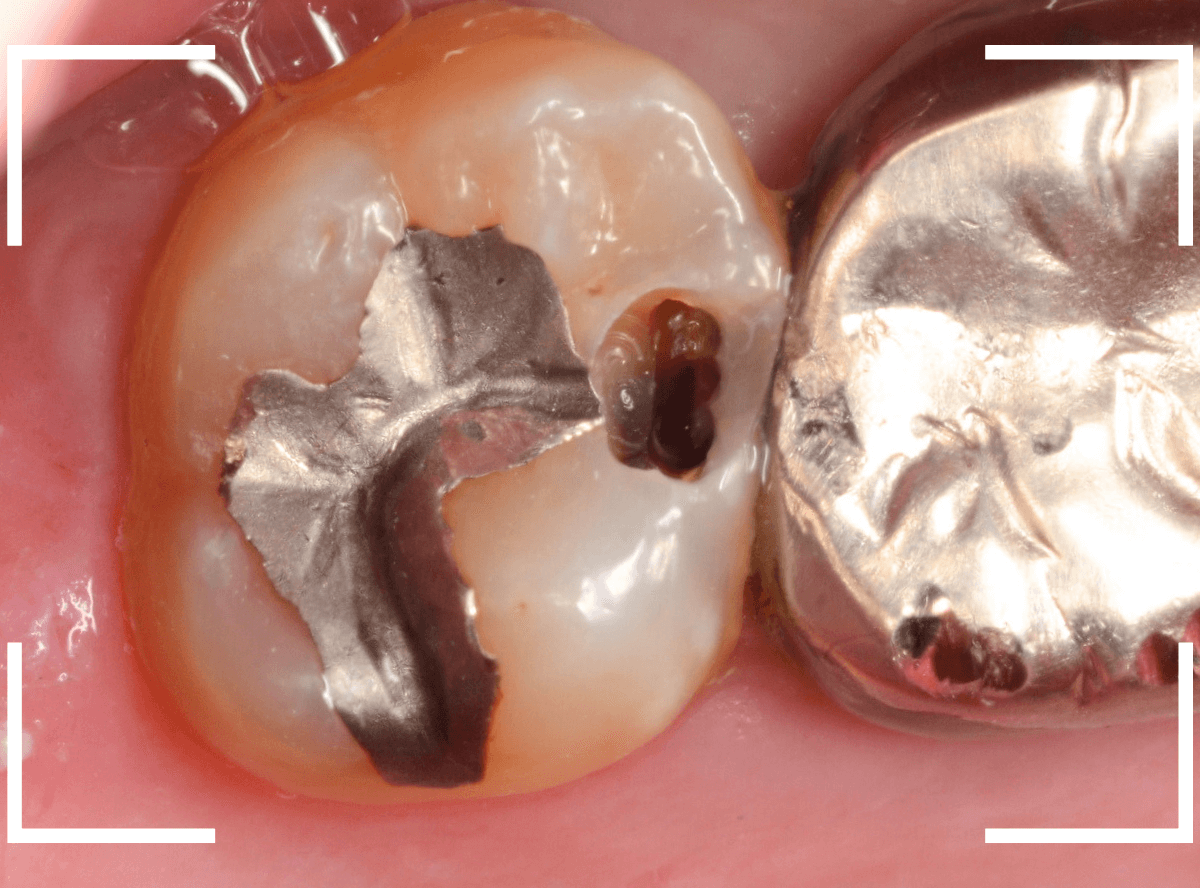

Case.23 歯のすきまから両側が大きな虫歯

「下の奥歯が痛む」という訴えで来院された患者さんのケースです。

目視でも、手前の奥歯がかけていて、中で虫歯が広がってるであろうことは予想できます。

ピンセットで歯を叩いてみても、手前の奥歯が痛むようです。

レントゲン写真で確認します。

青い線が神経、赤い線が虫歯の範囲です。

奥歯の方がより深い虫歯に見えますが、再度打診で確認したところ、やはり手前の奥歯が痛むそうです。

状況から、まず手前の奥歯から治療となりました。

麻酔をして、手前の奥歯のレジンを慎重に外します。

前に虫歯の治療をした時点で、神経スレスレの状態でしたので、削りすぎないように慎重にレジンを外さなければいけません。

レジンを外して、う蝕検知液で確認します。

レジンの中で虫歯が進行していたのがわかります。

慎重に全ての虫歯を除去しました。

何とか、神経が露出せずに済んでいます。

お薬をつめて、セメントで蓋をして経過観察します。

後日、状況を確認したところ、虫歯処置した後も、手前の奥歯が痛むとの事でした。

「我慢できないほどでもない」との事でしたので、引き続き経過観察しつつ、奥歯の治療を治療する事になりました。

奥歯は、レントゲンで見た通り、少し歯を削るとすぐに虫歯の穴が出てきました。

こちらは、ある程度虫歯を取ったところで染め出してみると真っ赤です。

ですが、何とか神経に達する前に、全ての虫歯を除去できました。

神経の治療が必要かと思っていたので、その点は幸運でした。

奥歯もお薬をつめて、セメントで蓋をして経過観察です。

何とか神経を取らずに済ませたいですが、どうなる事か・・・。